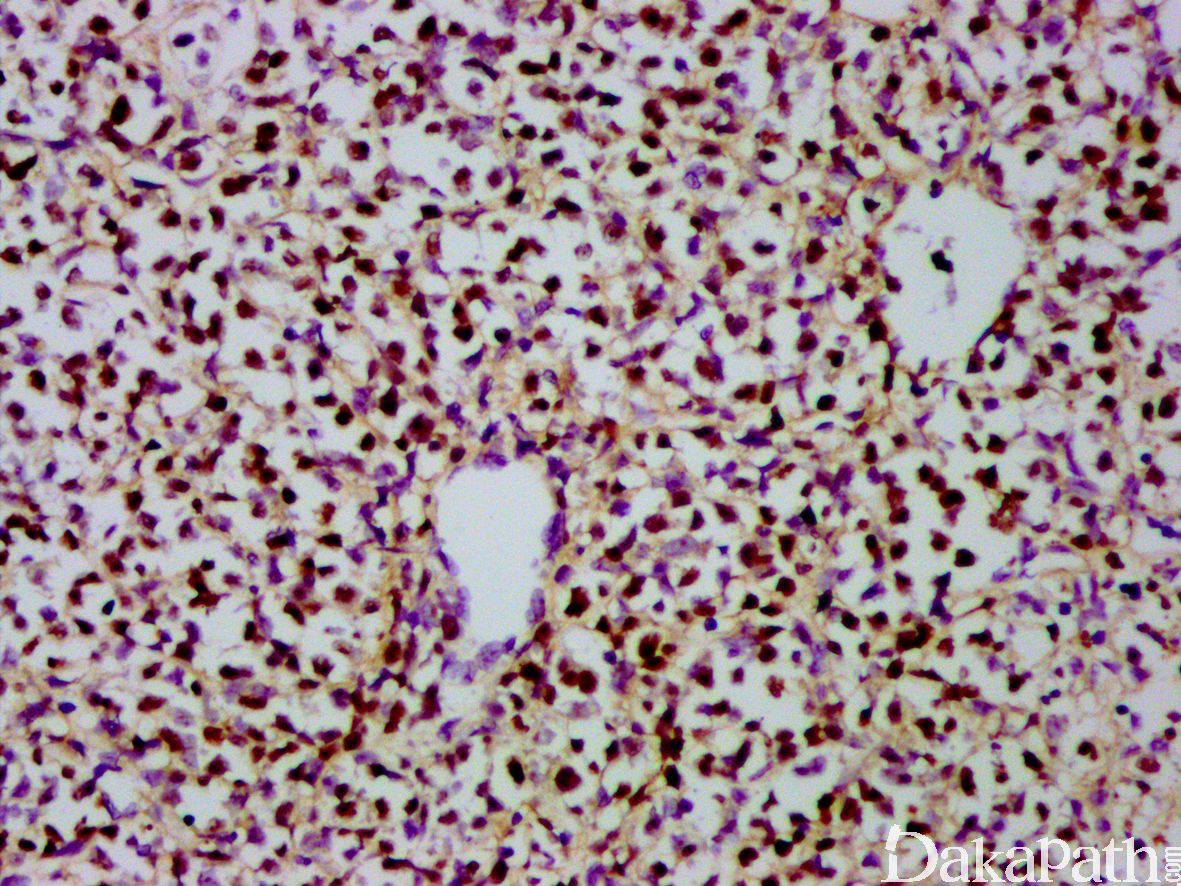

- 细胞形态及免疫表型同其它部位鼻型结外 NK/T 细胞淋巴瘤,EBV 常阳性。

EBER 原位杂交阳性